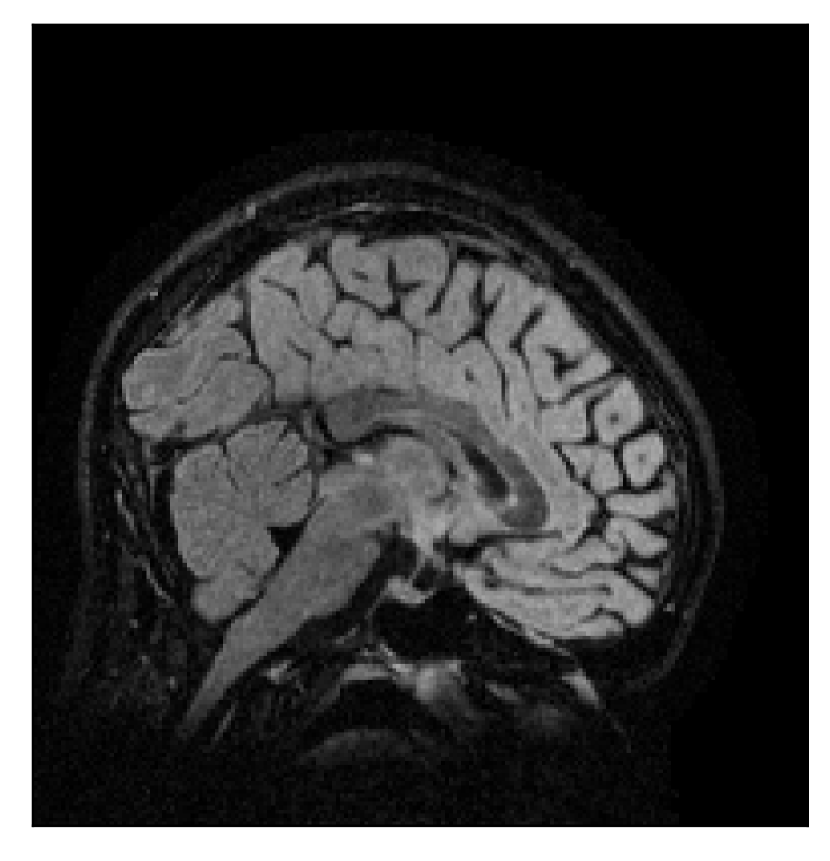

In the first experiment, we asked volunteer 3 to change position once during the prospectively-corrupted acquisition. We consider a corrupted T2-weighted contrast and a reference T1-weighted contrast (see Table 1). One important aspect of this experiment is related to the acquisition protocol of the T2-weighted contrast, based on a linear-filling pattern in -space. The corrupted data used as input for the proposed motion-correction algorithm is obtained by exporting the reconstructed volume directly from the scanner, followed by a simple Fourier transform. Note that this 3D image has been obtained by a SENSE reconstruction.

| Section 3.3, Figure 12 | Sagittal | 22.26 | 27.54 | 0.6963 | 0.8409 |

| Coronal | 23.46 | 31.65 | 0.7321 | 0.8370 | |

| Axial | 24.55 | 32.33 | 0.7895 | 0.8144 | |

The motion-corrected full-volume scans were analyzed by a neuroradiologist with 16 years of experience. These were generally deemed of good radiological quality. The motion-related artifacts have been completely removed, and the results are quite close to the ground truth. In Table 3, we organized a more detailed qualitative analysis of the 3D results, geared toward a radiological assessment of the corrected scans.

| Section 3.3, Figure 12 | T2 | Completely corrected | No blurring | No additional artifacts | |

4.3 Experiment 3: scanner reconstruction vs raw k-space data

The results of the two experiments described in Section 3.3 are depicted in Figures 12 and 14. The main difference between the two experiments is related to the input data for the proposed motion-correction algorithm.

In the first experiment, the corrupted contrast has been acquired with a protocol based on a linear filling pattern in -space. Note that, in this particular case, the scanner reconstruction implements the SENSE method. We then extracted the DICOM of both amplitude and phase produced by the scanner, and used it as input data (after a Fourier transform) for the algorithm. The proposed scheme is able to successfully remove the motion artifacts in Figure 12.

The method here presented is limited to rigid motion. Indeed, some decrease in correction quality is noticeable in Figure 12 in the neck region (which is not supposed to behave rigidly). However, our technique may be extended to non-rigid motion and, hence, different body regions other than the brain [see, for example, Huttinga et al., 2020]. A major challenge for such extension is a computationally effective parameterization of the motion effects, and the resulting ill-posedness of the inverse problem. Note that a significant computational advantage of rigid motion over non-rigid motion is related to the direct implementation of the rigid motion in -space, via equation (3), which results in a data model that requires a single NUFFT evaluation, regardless of the number of time samples considered. Other interesting extensions of the method are related to the integration of specialized motion-resilient acquisition patterns, e.g. as described in Cordero-Grande et al. [2020].